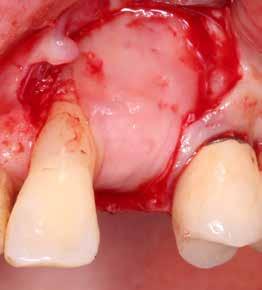

A korai harmicas éveiben járó hölgy rendelőnkbe érkezésének oka a jobb felső nagymetsző fog bizonytalan érzkenysége, elmondása alapján gyermekkorában trauma érte a felső frontrégiót. A frakturált klinikai koronákat kompozittöméssel helyreállították, egyéb kezelést akkor nem tartottak szükségesnek. Az utóbbi hónapokban tapasztalt érzékenység miatt kereste fel rendelőnket. A klinikai vizsgálat (1. és 2. kép) és a CBCT felvétel (3. kép) alapján diagnosztizált külső gyökérreszorpció megoldására a fog eltávolítását, implantátum

bukkális 1. kép: Kiindulási állapot, 2020. január. 3. kép: Kiindulási CBCT felvétel. 2. kép: Kiindulási állapot a palatinális oldal felől.

falat mint „pajzsot”, meg kell őrizni, ezzel megelőzhető a bukkális csontfal egyébként fiziológiás reszorpciója (4. és 5. kép). A sebészi technika különös körültekintést követel meg, nehogy a bukkális „gyökérpajzs” megmozduljon, ezzel a bukkális oldalon megmaradt periodontális ligamentumok sérülését kockáztatnánk, amely az esetenként